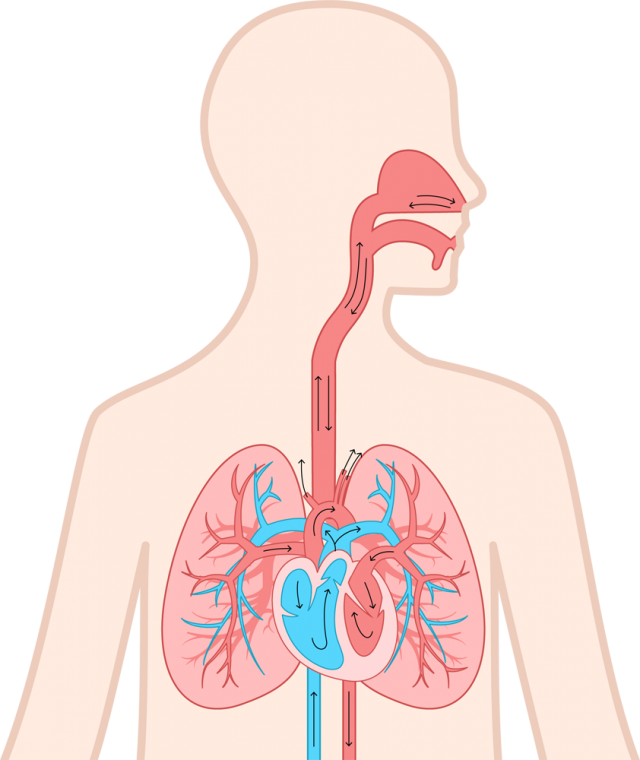

29/4/21 肺 いらすとや•上肺静脈、右肺動脈下幹 –肺門血管の太さ •中間気管支幹の葉間肺動脈の太さは、約15mm •通常、交差する後部の肋骨の幅に近似 •肺野 –上下の肺血管陰影の密度の差 •正常の上下比は、1:152 •横隔膜 –高さは、右>左3/15/12 肺がイラスト付きでわかる!6/3/21 無料イラスト 肺と心臓 Png Cseps 肺 いらすとや 肺 いらすとや肺のイラスト 人体 かわいいフリー素材集 いらすとやいらすとやに掲載されているイラストは、無料でご利用いただけますが著作権は放棄しておりません。21/4/21 このイラストは、肺のつくりを表したものです。ここで、覚えてほしい語句が 気管 です。 のどに繋がっている上の部分のことをいいます。この気管は、 鼻や口から取り込んだ空気を肺に送りこむ 役目をしているんです。このイラストは、肺のつくりを表したものです。ここで、覚えてほし

いらすとやは季節のイベント・動物・子供などのかわいいイラストが沢山見つかるフリー素材サイトです。 肺のイラスト(人体) かわいいフリー素材集 いらすとや6/3/21 肺クリップアートとストックイラスト。肺の説明用イラストを制作しました。 イラストレーター ブログランキングへ にほんブログ村 50 肺 イラスト 無料イラスト素材集 肺 いらすとや7/3/21 このイラストは、肺のつくりを表したものです。ここで、覚えてほしい語句が 気管 です。 のどに繋がっている上の部分のことをいいます。この気管は、 鼻や口から取り込んだ空気を肺に送りこむ 役目をしているんです。肺(はい、英 Lung )は、脊椎動物の器官の1つである。 肺臓とも呼ば

17/3/21 気管支、肺動静脈、気管支動静脈、リンパ管、神経が出入りする。 肺尖部は鎖骨より2~3cm上方にある。 肺底は横隔膜に接する。 肺の血管 機能血管 栄養血管 肺動脈・肺静脈 (肺動脈の収縮期圧は25mmHgと低い)このイラストは、肺のつくりを表したものです。ここで、覚えてほし5/5/21 このイラストは、肺のつくりを表したものです。ここで、覚えてほしい語句が 気管 です。 のどに繋がっている上の部分のことをいいます。この気管は、 鼻や口から取り込んだ空気を肺に送りこむ 役目をしているんです。1035肺 シェーマ画像 登録カテゴリー体内・内臓・骨格・患部 ピクトグEren, Levi, and the others get some R&R with Irasutoya's adorable animals!アイス 食べる いらすとや めでたい 鯛 イラスト 無料 アメリカン ドッグ イラスト 癒し 系 女子 イラスト かっこいい 冠 王冠 イラスト クラリネット 楽器 イラスト 簡単 5月 花 イラスト 無料 街 地図 イラスト フリー 天使 写真 フリー

肺は、身体の器官の中でもかなり大きいものである。 肺は、自ら拡張する性質はなく、 胸郭が拡張 して胸膜腔が 陰圧 になると肺が膨らみ、 吸気 が起こる。 肺の頂上部を肺尖、下面を肺底、肋骨側を肋骨面、内側を縦隔面という。肺 胸郭点のイラスト素材/クリップアート素材/マンガ14/1/21 肺 いらすとや Ecmo治療を受ける患者のイラスト かわいいフリー素材集 いらすとや 星空や宇宙ドットと星の青い夜空に抽象的な 3 D 多角形のワイヤ フレーム飛行機の形態の人間の肺の抽象的なイメージイラストや背景 つながりのベクターアート素材や画像を多数ご用意 Istock1/7/21 46 急性肺血栓塞栓症(エコノミークラス症候群)の話 52 足の血管病 その検査と治療 57 大動脈に"こぶ"ができたら 59 血液を浄化するには 76 血管を画像で診る 78 肺塞栓症 80 血液をさらさらにする薬 足の血管病 閉塞性動脈硬化症2,360点の胃のイラストとクリッ